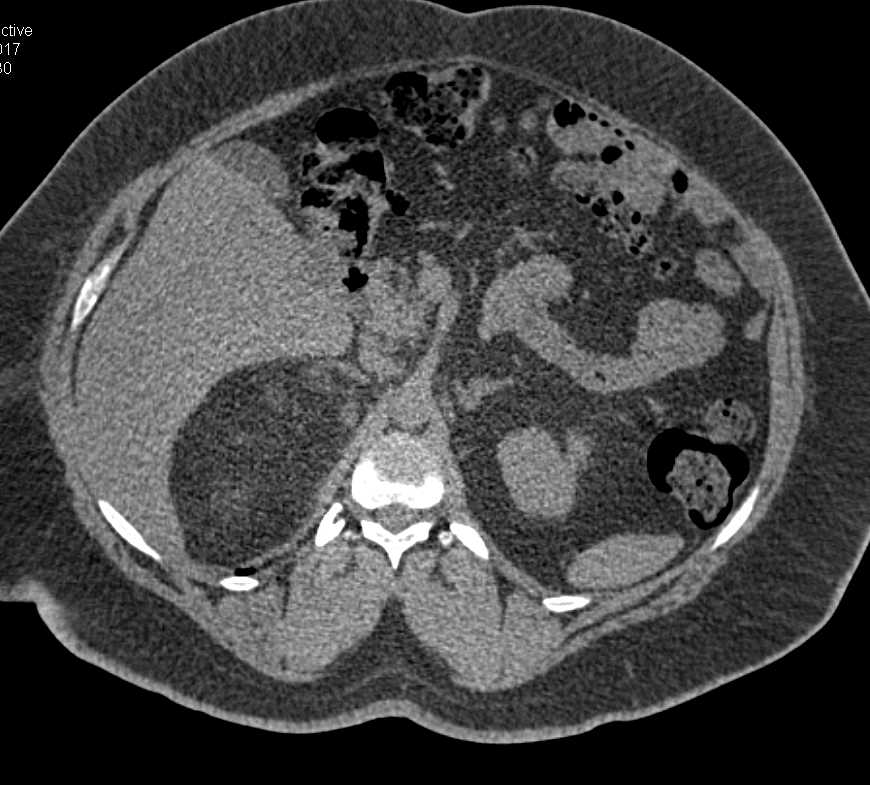

Right Adrenal Myelolipoma